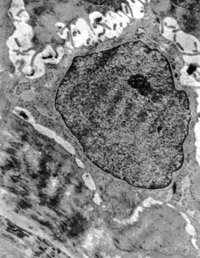

5-2-2 伤后第1天,,,,,,,毛细血管内皮细胞核固缩,,,,,,,管腔内血液凝集和瘀滞  TEM×6000